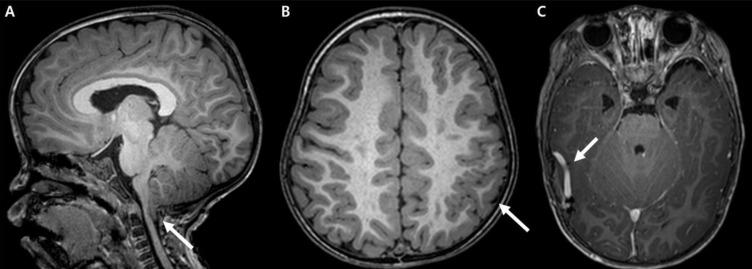

巨头畸形-毛细血管畸形-多小脑回综合征:韩国首例病例报告。

Megalencephaly-capillary malformation-polymicrogyria syndrome: the first case report in Korea.

Megalencephaly-capillary malformation-polymicrogyria syndrome (MCAP), previously known as macrocephaly-cutis marmorata telangiectatica congenita and macrocephaly-capillary malformation syndrome, is a rare multiple-malformation syndrome that is characterized by progressive megalencephaly, capillary malformations of the midline face and body, or distal limb anomalies such as syndactyly. Herein, we report a female infant case that satisfies the recently proposed criteria of MCAP and describe the distinctive neuroradiological and morphological features. We have also reviewed recently published reports and the diagnostic criteria proposed by various authors in order to facilitate the clinical diagnosis of these children in pediatric neurology clinics.

巨脑回-毛细血管畸形-多小脑回综合征(MCAP),以前称为先天性大理石样皮肤毛细血管扩张性巨头畸形和巨头畸形-毛细血管畸形综合征,是一种罕见的多发畸形综合征,其特征为进行性巨头畸形、中线面部和身体的毛细血管畸形或诸如并指等远端肢体异常。在此,我们报告一例符合最近提出的MCAP标准的女婴病例,并描述其独特的神经放射学和形态学特征。我们还回顾了最近发表的报告以及各位作者提出的诊断标准,以便于儿科神经科诊所对这些儿童进行临床诊断。